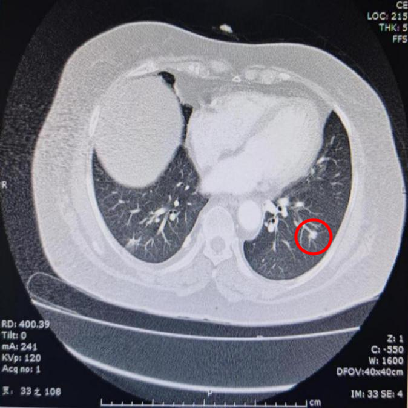

基本信息:性别 女,年龄 78岁,身高 159cm,体重 62kg。 主诉:结肠癌及肝转移瘤术后2年6个月(首次就诊时间为2018-09-10)。 既往史、个人史:“2型糖尿病”20年,予“二甲双胍 0.5g 口服 2次/日、门冬胰岛素注射液皮下注射,早 30U,晚 28U;甘精胰岛素皮下注射 20U ”降糖治疗,血糖控制一般。 家族史:无特殊。 02 初诊病史 体格检查、B超、CT及其他辅助检查。 体表面积1.60m,体格检查:浅表淋巴结未及肿大,双肺呼吸音粗,未闻及干湿性啰音,心律规整,未闻及杂音,腹壁可见陈旧性手术瘢痕,愈合良好,腹软,未及肿物,无压痛,肛查-,双下肢无水肿,起病隐匿,体检行腹部超声发现肝脏占位。 肠镜(2016-3-12):乙状结肠肿物。 咬检病理:(乙状结肠)腺癌。 肝胆胰增强CT(2016-3-10):肝左叶占位。 考虑:乙状结肠癌Ⅳ期 肝转移。 2016-3-21 于外院行“乙状结肠癌根治术+肝左叶转移瘤切除术”,术中予输血治疗,术后恢复慢,切口延期愈合。 术后病理:结肠中分化腺癌伴坏死形成,大者3.5cm×3.2cm×0.5cm,癌组织侵及浆膜脂肪层,脉管内癌栓形成,小者1cm×1cm×0.5cm,癌组织侵及粘膜下层。肠壁周围淋巴结癌转移(3/6),T3N1M1。(肝左叶)肝脏转移性腺癌伴大片坏死形成,大小6.6cm×6cm×4.5cm,结肠来源,残端及吻合口上下缘肠壁未见肿瘤侵及。 基因检测:KRAS、NRAS、BRAF 均未见突变。 初步诊断:乙状结肠癌Ⅳ期(pT3N1M1),同时性肝转移,中分化腺癌,2型糖尿病。 03 治疗方案 2016-4 XELOX 方案化疗1周期(具体剂量不详)因不良反应较重,未完成术后辅助治疗疗程。未予后续治疗,定期复查,病情稳定 胸腹CT(2017-3-19 ):右肺下叶新结节,考虑转移;肝左外叶转移瘤切除术后改变。 2017-4-1 于外院行局部肺肿物射频消融术,无治疗反应,恢复良好。 胸CT(2017-12-5):肺部新发结节,考虑转移。 【一线治疗方案(2017-12至2018-9)】 卡培他滨 1.5g po d1-14 q3w,共10个周期。 不良反应:1度消化道反应。 期间疗效评价:SD。 胸腹增强CT(2018-9-11):符合结肠癌切除术后,肝左叶切除后改变,双肺多发结节,部分较前增大。 2017-12-5 2018-9-11 建议调整方案治疗,患者家属拒绝,继续口服卡培他滨至2019年3月。 疗效评估: ECOG PS评分1分,新发活动后胸闷、气短症状 胸腹平扫CT(2019-3-26):双肺多发结节,较前增大;肝左外叶转移瘤切除术后改变。 2018-9-11 2019-3-26 评估PD。 【二线治疗方案(2019-4至2020-5)】 贝伐珠单抗 300mg ivgtt d0(体重62kg); 卡培他滨 1.5g po d1-14 q3w,共15周期。 不良反应:1级高血压、1度消化道反应。 疗效评估: 胸腹CT(2020-5-21):符合结肠癌术后、肝左叶切除术后,肝左切缘旁异常密度灶,左髂总动脉旁淋巴结;双肺多发结节,部分较前增大,右肺门肿物较前增大。 疗效评价:PD。 【三线治疗方案(2020-5至2020-10)】 西妥昔单抗 600mg ivgtt d0(体表面积1.66 m2); 亚叶酸钙 500mg ivgtt d1; 氟尿嘧啶 500mg ivgtt ,随后3500mg iv泵入 q2w,共9周期。 不良反应:无皮疹、腹泻、恶心、呕吐等。 疗效评估: 胸腹平扫CT(2020-09-07):右肺下叶背段软组织肿块,较前略减小,双肺多发小结节,转移瘤,同前;结肠癌术后、肝左叶切除术后改变,肝左切缘旁异常密度灶同前相仿,腹膜后左侧髂总动脉旁淋巴结同前。 2020-7-23 2020-9-7 疗效评价:SD(缩小趋势)。 胸腹平扫CT(2020-10-24):右肺下叶背段软组织肿块,较前(2020-9-7)略减小,双肺多发小结节,转移瘤,部分较前减小,结肠癌术后、肝左叶切除术后改变,肝左切缘旁异常密度灶同前相仿,腹膜后左侧髂总动脉旁淋巴结同前。 2020-9-7 2020-10-24 疗效评价:SD(缩小趋势)。 胸腹平扫CT(2020-12-13):右肺下叶背段软组织肿块,较前(2020-10-24)未见著变,双肺多发小结节,转移瘤,较前未见著变,结肠癌术后、肝左叶切除术后改变,肝左切缘旁异常密度灶同前相仿,腹膜后左侧髂总动脉旁淋巴结同前。 2020-12-13 疗效评价:SD。 患者未规律返院行西妥昔单抗维持治疗。 胸腹增强CT(2021-1-5):右肺下叶背段软组织肿块,较前(2020-12-13)增大,双肺多发小结节,转移瘤,左肺尖结节较前增大,余未见著变,左侧髂总动脉旁淋巴结较前增大。 疗效评价:PD。 【四线治疗方案(2021-1至2021-10)】 安罗替尼 8mg po 1次/日 d1-14 (2021-3 起因高血压2级,药物控制不佳调整为8mg qod ); 卡培他滨 1g po 2次/日 d1-14 q3w (2021-4 起因乏力2级不能耐受停服)。 不良反应:2级高血压,2级乏力,1级胆红素升高,1度消化道反应。 疗效评估: 胸腹增强CT(2021-10-3):右肺下叶背段占位,考虑恶性肿瘤,较前增大,双肺多发转移瘤,部分较前略增大,结肠癌术后、直肠区肠管明显扩张,肝左叶切除术后改变,切缘旁占位伴肝内胆管扩张,累及胆总管,考虑恶性病变,较前增大,腹膜后左侧髂总动脉旁淋巴结,较前增大,累及左侧输尿管伴以上输尿管及肾盂扩张。 2021-10-3 疗效评价:PD。 疗效评估: 胸腹增强CT(2021-10-3):右肺下叶背段占位,考虑恶性肿瘤,较前增大,双肺多发转移瘤,部分较前略增大,结肠癌术后、直肠区肠管明显扩张,肝左叶切除术后改变,切缘旁占位伴肝内胆管扩张,累及胆总管,考虑恶性病变,较前增大,腹膜后左侧髂总动脉旁淋巴结,较前增大,累及左侧输尿管伴以上输尿管及肾盂扩张。 【后线治疗方案(2021-10至2021-11)】 曲氟尿苷替匹嘧啶片(TAS-102) 40mg po 2次/日 d1-5,d8-12,q4w; 贝伐珠单抗 200mg ivgtt q2w。 不良反应:无皮疹、腹泻、恶心、呕吐等。 疗效评估: 胸腹增强CT(2021-11-17):右肺下叶背段占位,较前变化不明显,双肺多发转移瘤,较前变化不明显,结肠癌术后、直肠区肠管明显扩张,肝左叶切除术后改变,切缘旁占位伴肝内胆管扩张,累及胆总管,考虑恶性病变,较前变化不明显,腹膜后左侧髂总动脉旁淋巴结,较前减小,肾盂扩张较前减轻。 疗效评价:SD。 胸腹增强CT(2021-11-17):右肺下叶背段占位,较前变化不明显,双肺多发转移瘤,较前变化不明显,结肠癌术后、直肠区肠管明显扩张,肝左叶切除术后改变,切缘旁占位伴肝内胆管扩张,累及胆总管,考虑恶性病变,较前变化不明显,腹膜后左侧髂总动脉旁淋巴结,较前减小,肾盂扩张较前减轻。 04 病例小结 患者为高龄女性,诊断为直肠癌Ⅳ期多发转移,KRAS、NRAS、BRAF 均未见突变。 OS为69个月。